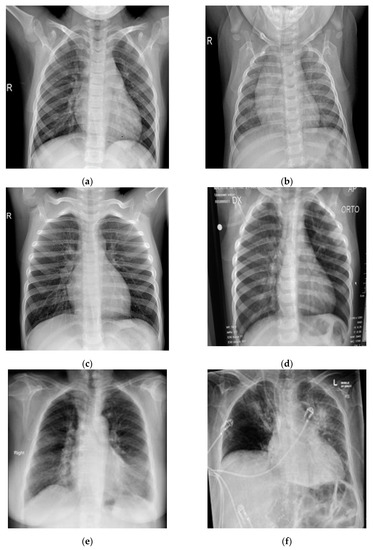

In this study, pulmonary (chest) X-ray images were used for the diagnosis of COVID-19. The dataset was categorized into two main classes, i.e., COVID-19 and normal. A total of 7232 images (3616 COVID-19 + 3616 normal) were accessed from the ‘COVID-19 Radiography Database (available at Kaggle, https://www.kaggle.com/tawsifurrahman/covid19-radiography-database, accessed on 4 May 2021) [30]. From the total images, 70% (5062 images) were used for training + validation, and the remaining 30% (2170 images) were used for testing purposes. The training + validation dataset of 5062 images was further split into a 70:30 ratio, i.e., 3544 (70%) images for training purposes and 1518 (30%) images for validation purposes. The details of the data splitting are given in Table 1. In addition to the dataset accessed via Kaggle, another locally collected dataset of 450 images (COVID-19 + normal) was also used for testing and prediction purposes. This indigenous data of chest X-ray images of Pakistani COVID-19 positive and normal patients have been collected from a local hospital. The samples of normal and COVID-19 X-ray images assessed via the Kaggle database are shown in Figure 1, whereas the samples of the locally collected images are given in Figure 2.

Figure 1.

Samples of chest X-ray images assessed via Kaggle database [30,31,32] for training purposes: (a–c) normal chest X-rays; (d–f) COVID-19 chest X-rays.